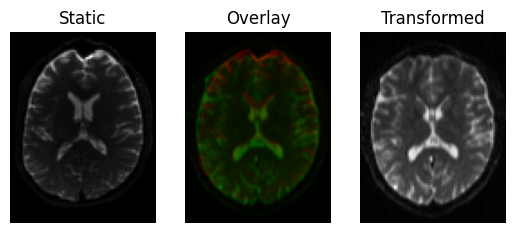

This results in a slight shear and scale

transformed = affine.transform(moving)

<Figure size 640x480 with 3 Axes>

Registration result with an affine transform, using Mutual Information.